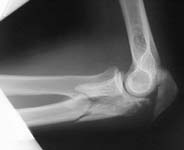

A manual labourer admitted to our unit couple of days afer a train accident with the open injury.

The wound is small, debrided in the initial hospital and shows no signs of infection at the moment.

As a first step an external fixator applied yesterday, with percutaneous screw fixation of the lateral epicondyle.

If no signs of infection he is ready for further procedures within few days. What plan is optimal for the case? Attempt of open reduction of the "mosaic" and plating? Early functional treatment without open procedures? Reinsertion of olecranon and small fragment removal? Total elbow replacement?